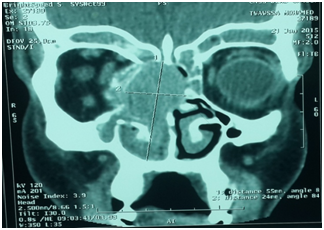

Mr. TM age 47 without antecedent of facial trauma, presenting for 5 months of intermittent epistaxis associated moderate has a right nasal obstruction and anosmia, the evolution was marked by exophthalmos with decreased visual acuity and headache intermittences, the objective endonasal examination has a burgeoning mass bleeding in contact obstructing the totality of the nasal cavity. The scan realized with contrast injection has evidence an extended tumor of the nasal cavity, orbit (Figure 2) the patient has benefited from a preoperative embolisation, and the operative act was marked by pleading at the slightest touch; after a multidisciplinary staff: decision of radiotherapy

Figure 2 Frontal sections: filling of the right nostril with lysis intersino-nasal wall and the iinner wall of the orbit.